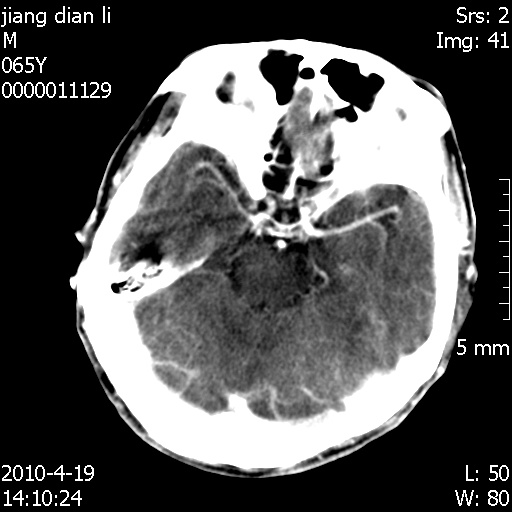

老年男性,突发左下肢无力1天,其余有价值的检查都没有。平扫ct值大约60hu,增强后ct值没什么改变,请大家讨论一下这个病例是什么?说明诊断理由。

左小脑、右大脑顶叶多发圆形高密度病灶,其周环状低密度影。考虑多发脑出血。隔期观察。

今天上班后发现病人前天复查(4月18日发病,19日初诊,22日复查),三个病灶均明显增大,边缘仍旧清楚,水肿加重,右侧脑室基本闭塞。

我想:如果是肿瘤出血的话,一般不会导致体积明显改变,水肿又进一步加重;如果是出血灶,那么现在应该正好是水肿加重的时候,还是比较符合,但是为什么边缘又是这样的特点?